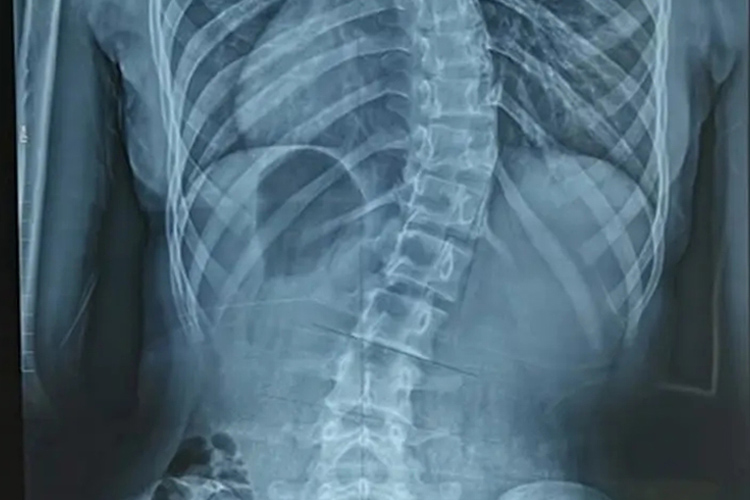

中重度脊柱侧弯:出现脊柱侧弯后仍未及时改正写字姿势,可能使脊柱侧弯逐渐加重,出现两侧肩胛骨高低不一致或体态畸形。严重畸形可引起内脏功能紊乱,如心、肺等发育不良,活动时常感到气促、心悸、胸闷等。体格检查可发现脊柱呈“S”形侧弯,背部一侧呈局限性隆起。

写字姿势不正确导致脊柱侧弯,是身体姿势不正、长期偏向一方、长期习惯于用一侧肩负重等原因所致,但也不排除机体同时存在下肢不等长、胸椎间盘突出等情况。可通过体格检查、X线片等方式进行诊断。